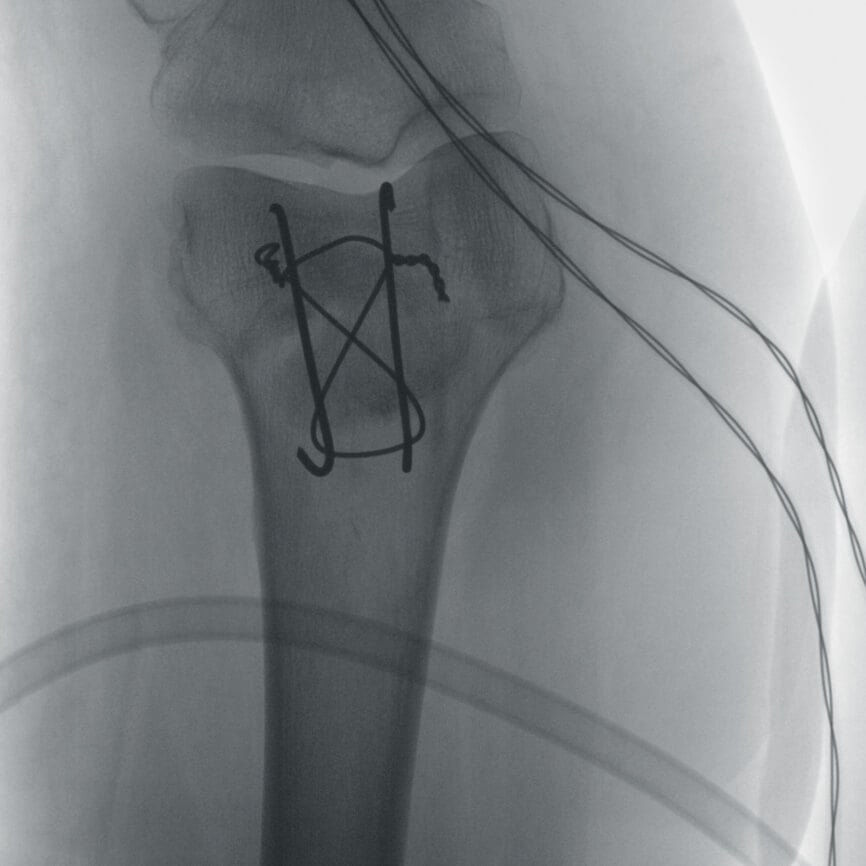

Полное отсутствие искажений снимков в сочетании с высоким динамическим диапазоном широко востребованы как при сложных операциях в нейрохирургии, сосудистой хирургии, инвазивной радиологии, так и в гибридных областях применения, а также в ортопедии, травматологии. В сосудистой хирургии особенно важны высокий динамический диапазон и пространственное разрешение, обеспечивающие детальную визуализацию даже мельчайших сосудов. Специализированное программное обеспечение SmartVascular позволяет проводить настройку системы для васкулярных операций и сосудистой хирургии.

Точная визуализация анатомических деталей, мягких тканей и костных структур обеспечивается за счет светочувствительной матрицы 3kх3k пикселей с высоким динамическим диапазоном.

Автораспознавание металла

Винты, пластины, импланты и хирургические инструменты автоматически распознаются при попадании в видимое поле аппарата. В этом случае происходит корректировка мощности дозы облучения для улучшения качества снимка.